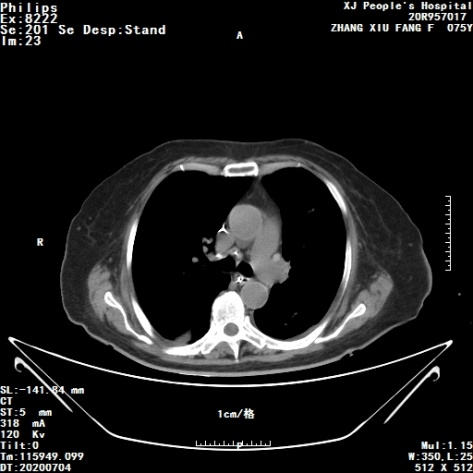

胸部CT

胸部CT结果如图1(2020年6月29日)所示:①左肺癌治疗后改变,左侧胸腔大量积液,左肺膨胀不全,较2020年6月23日积液增多;②右肺炎性病变,较前进展;③左肺门转移淋巴结可能,同前;④纵隔内淋巴结转移可能,同前;⑤右侧胸腔积液,较前增多。

图1 胸部CT(2020-06-29)